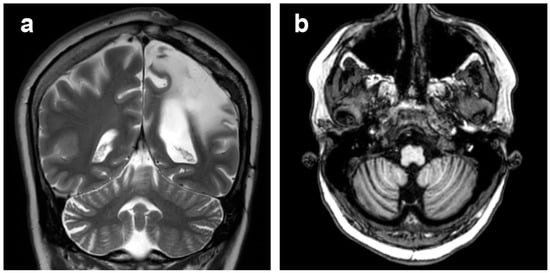

3.1. Atrophic Changes

3.2. Changes in Signal Intensity